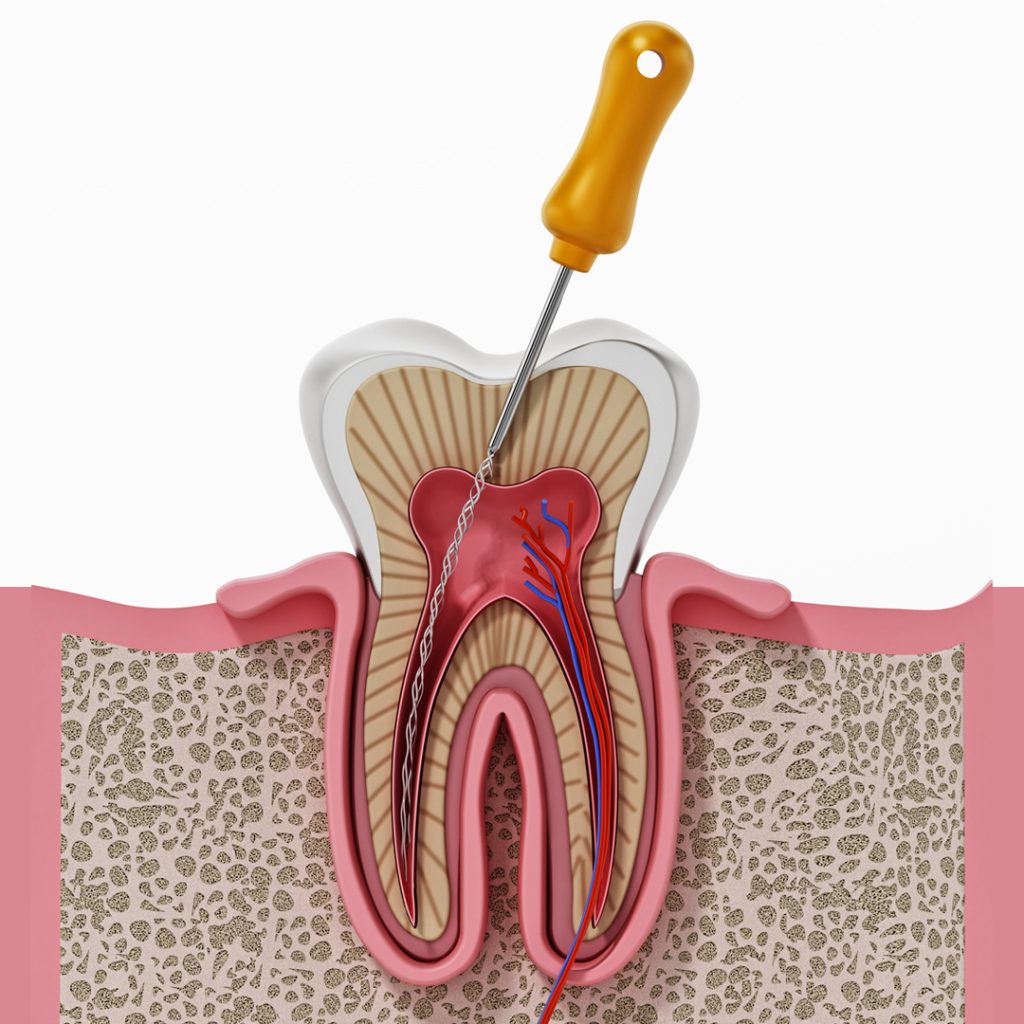

Diş kanal tedavisi, dişin içindeki canlı dokunun çürümesi veya hasar görmesi sonucu oluşan iltihaplanma ve ağrıların tedavisi için uygulanan bir işlemdir. Bu tedavi, dişin canlı dokusunu oluşturan sinirler ve kan damarlarına ulaşmak için dişin çürümüş veya hasar görmüş bölgesinin açılması ve temizlenmesi işlemidir… devam